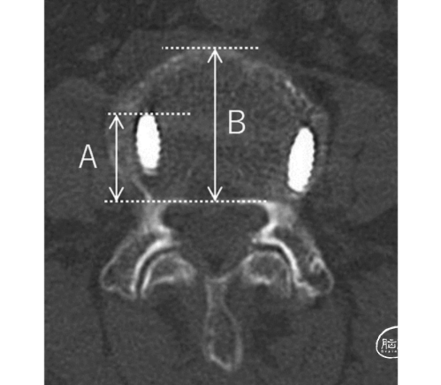

日本东京国立医院骨外科的Keitaro Matsukawa等通过影像学检查评估CBT术后螺钉松动和骨融合状况,分析螺钉插入深度对腰椎融合术的影响,阐明螺钉直径、螺钉长度、螺钉在椎体中的深度(深度百分比)等影响预后的因素(图2)。结果发表于2021年8月《Journal of Neurosurgery:Spine》在线。

图2. 螺钉插入深度评估。深度百分比(% depth)定义为轴向平面上椎体内螺钉长度(A)与椎体前后缘长度(B)的比值。